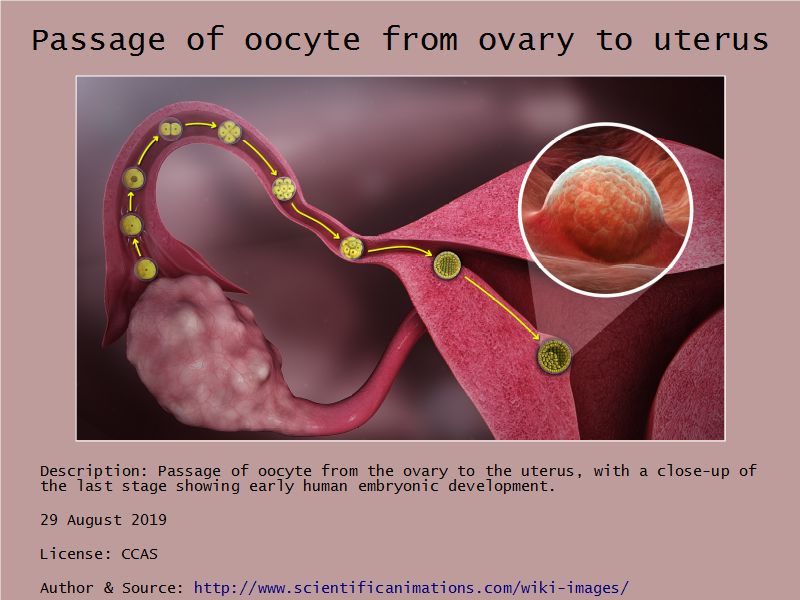

Tuba uterina

Tuba uterina

- Muscular tube

- Most frequent site of fertilization

- Conveys zygote to uterus

- Four regions

- Ampulla

- Usual site of fertilization

Mucosa

- Epithelium

- Lamina propria

Epithelium

- Simple columnar

- 2 types of cells

- Peg cells

- Secretory cell

- Ciliated cells

- Beats towards uterus

- Facilitate movement of zygote to uterus

Lamina propria

- Loose connective tissue

- Reticular fibres

- Fibroblasts

- Mast cells

- Lymphoid cells

Muscular layer

- Ill-defined

- Inner circular

- Outer longitudinal

- Play role in moving zygote towards uterus